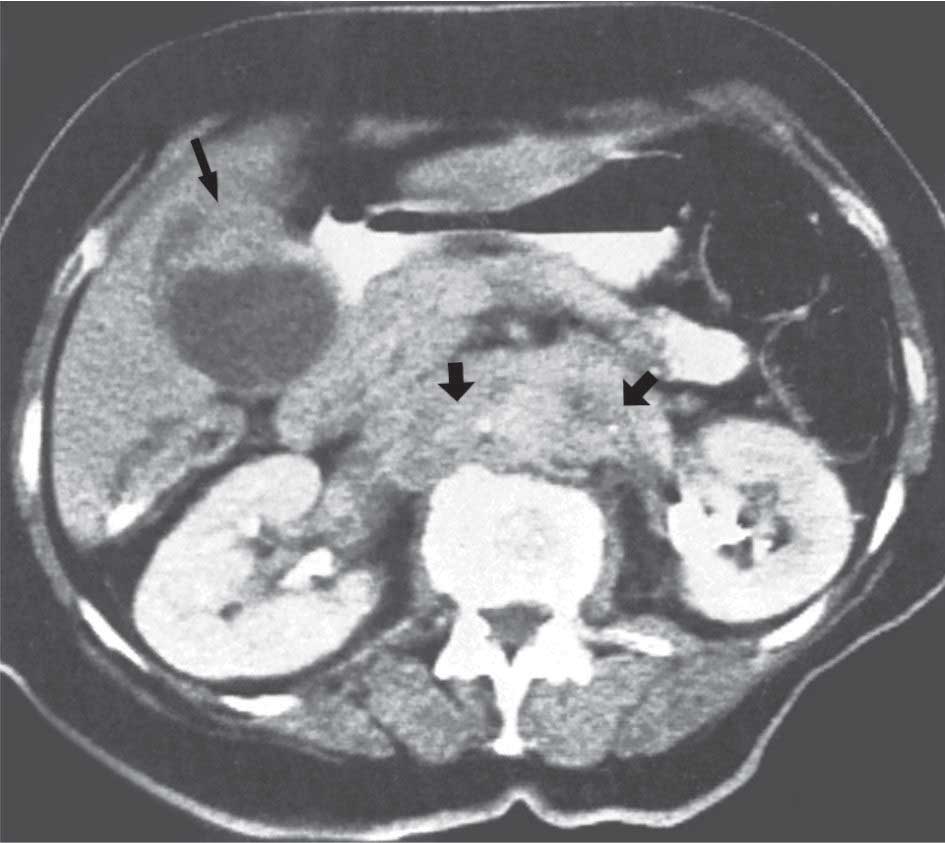

| الشكل (3) صورة المرارة بالأمواج فوق الصوتية تكشف وجود كتل سليلانية الشكل ملتصقة بجدار المرارة لا يتبدل موقعها عند تبدل وضعيةا لمريض تمثل أوراماً كوليسترولية | الشكل (4) سرطانة المرارة: يبين التصوير المقطعي المحوسب وجود كتلة من النسيج الرخو على طول الجدار الأمامي للمرارة (السهم المستقيم). يلاحظ وجود نقائل عقدية جانب الأبهر (السهم ا منحني) |

- سرطانة المرارة gallbladder carcinoma: يمكن للتصوير بتخطيط الصدى أن يضع التشخيص في 80% من الحالات إذ يَظهر الورم على شكل تنبت غير متحرك داخل لمعة المرارة أو على شكل عدم انتظام في جدارها. يكون التشخيص صعباً في حال وجود حصيّات مرارية مرافقة من جهة- وهي مصادفة كثيراً- وامتداد الورم إلى النسيج الكبدي المجاور من جهة أخرى والذي يصعُب معه تحديد منشأ الورم. أما التصوير المقطعي المحوسب فإنّه يُعطي معلومات مماثلة عن الورم في حين يحدد امتداد الورم بشكل أفضل، وكذلك الحال فيما يخص الرنين. إنّ تخطيط الصدى عبر التنظير هو أكثر وسيلة حساسية لدراسة الورم وامتداده عبر طبقات جدار المرارة وإلى النسيج الكبدي المجاور. أما التنظير الراجع فليس له استطباب هنا إلاّ إذا كان هناك استطباب له بوصفه إجراءً علاجياً.

2- التصوير المقطعي المحوسب computed tomography (CT-scan): لا يُعتمد عليه في دراسة المرارة؛ ولاسيما لدراسة الحصيات المرارية. أما فائدة دراسة الطرق الصفراوية فهي محدودة أيضاً إلاّ في الآفات الورمية حيث يعطي معلومات جيدة عن توضع الآفة وانعكاسها على الشجرة الصفراوية (توسع القنوات) فوق الآفة؛ وأخيراً امتدادها الناحيّ والبعيد. كما يمكن بهذه الطريقة أخذ خزعة موجهة عبر الجلد.